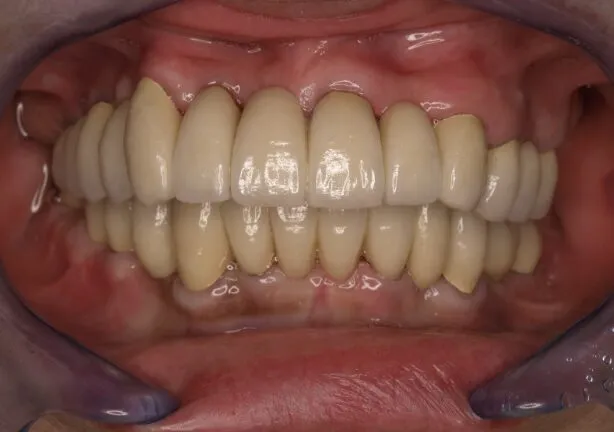

After